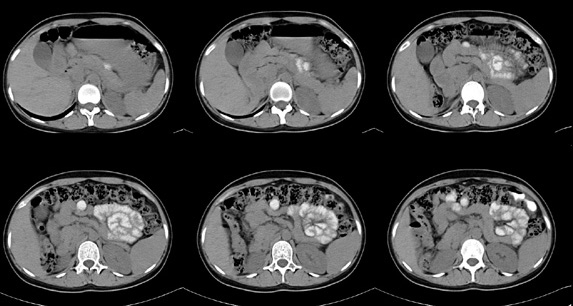

女性,28岁,停经3月,腹部膨隆1月,产前检查发现腹部占位

{肿块中心ct值27hu,增强后,动脉期、门脉期均无明显强化)

患者手术病理:腹腔囊性淋巴管瘤,象这样充满整个腹腔的的确很少见